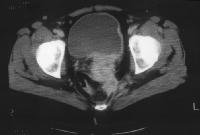

Stage Ib carcinoma confined to the cervix. CT image shows a mass with slightly heterogeneous area of attenuation expanding the cervix and surrounded by a thin rim of relatively preserved stroma. The cervical margins are smooth, well defined, and intact. Parametrial soft-tissue stranding or masses are lacking, and the periureteral fat planes are preserved. Cervix, cancer. CT image depicts a large lobulated mass replacing the cervix and showing non-uniform hypoattenuation. The air and fluid in the center of the mass are consistent with tumor necrosis and complicating infection (the patient had purulent discharge). The central hypoattenuation in the uterine corpus is suggestive of minimal fluid in the cavity.